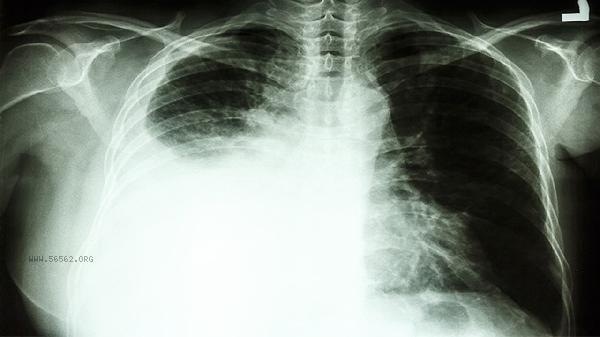

The discovery of elevated CEA requires further imaging and pathological examination. It is recommended to perform low-dose chest CT screening for lung lesions. For those with gastrointestinal discomfort, gastrointestinal endoscopy should be performed to evaluate the digestive tract condition, and other tumor markers such as CA199 and CA724 should be tested to assist in judgment. Daily smoking cessation and alcohol restriction are necessary to avoid excessive anxiety. Regular monitoring of changes in indicators should be conducted, and a diagnosis should be made by a specialist doctor based on clinical manifestations and other examination results.